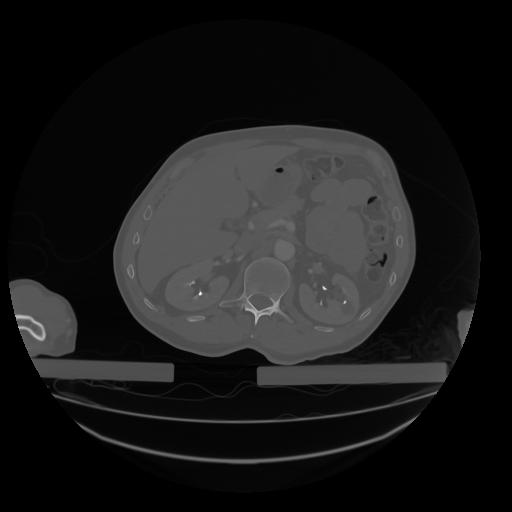

28 CUERPO,CE,Vol,2.0,CUERPO,,